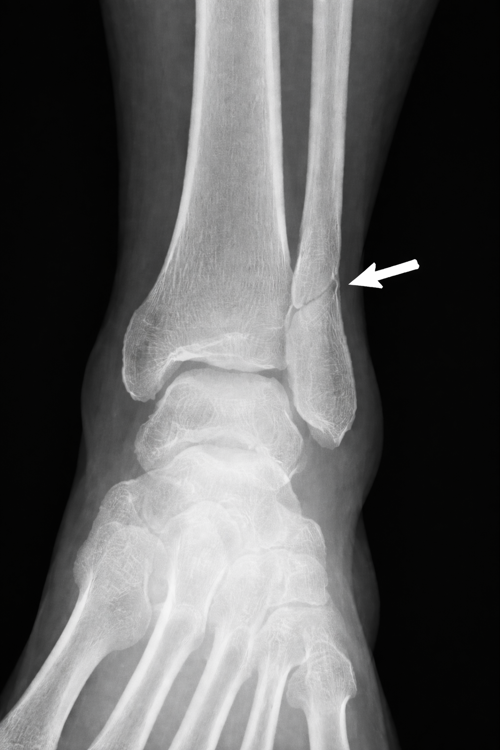

Figuur 1

Een Weber B-fractuur komt vaak voor. Het is een breuk van het kuitbeen ter hoogte van de enkelbandverbinding (syndesmose). Uit de röntgenfoto’s blijkt dat het bij u om een stabiele Weber B-fractuur gaat. Dit betekent dat u 1 tot 2 weken gips zult krijgen, waarbij het belangrijk is dat u niet loopt. Na deze periode krijgt u een enkelbrace en kunt u, afhankelijk van de klachten, geleidelijk gaan belasten voor een periode van 4 tot 5 weken. Zes weken na de breuk komt u terug voor een controle op de gipskamer.

Een breuk in het kuitbeen komt vaak voor. Uit de extra röntgenfoto's blijkt dat u een stabiele breuk heeft. U krijgt 1 tot 2 weken een gipsverband, waarmee u niet mag lopen. Daarna krijgt u een enkelbrace, zodat u rustig kunt beginnen met belasten.